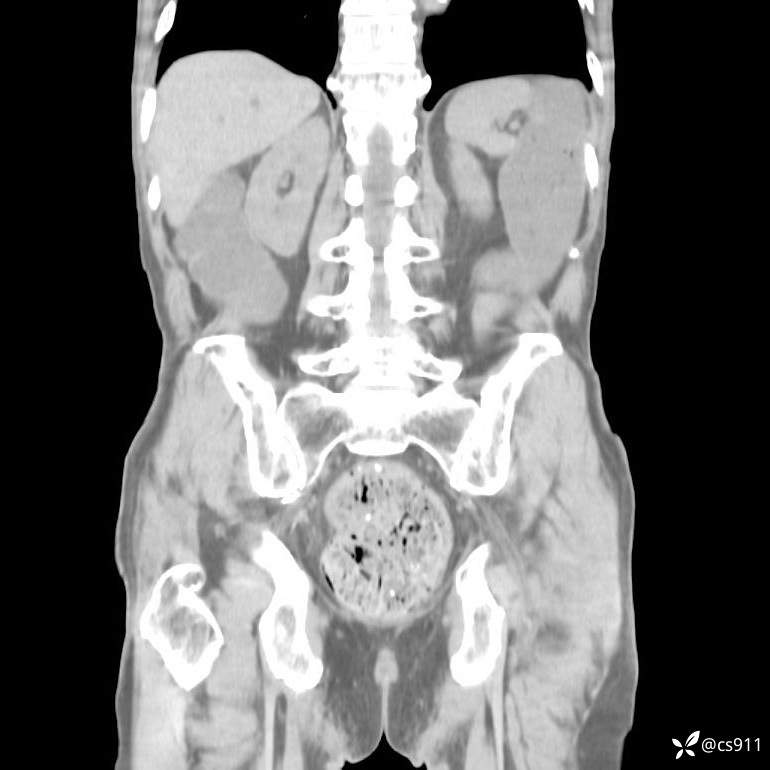

急腹症之急诊CT,原因?答案公布

男,77岁,腹痛、腹胀伴恶心呕吐1天。呕吐胃内容物,非喷射性呕吐,有咖啡色样胃内容物,诉有胃穿孔病史。查体:全腹平,下腹部压痛,全腹无反跳痛,叩诊呈浊音,移动性浊音阴性,肠鸣音减弱,1-2次/分。肛检:直肠未扪及明显肿物,可触及大量粪块。

血淀粉酶(AMY) HH 1859 U/L 35-135

癌胚抗原(CEA) H 27.44 ng/ml 0-5